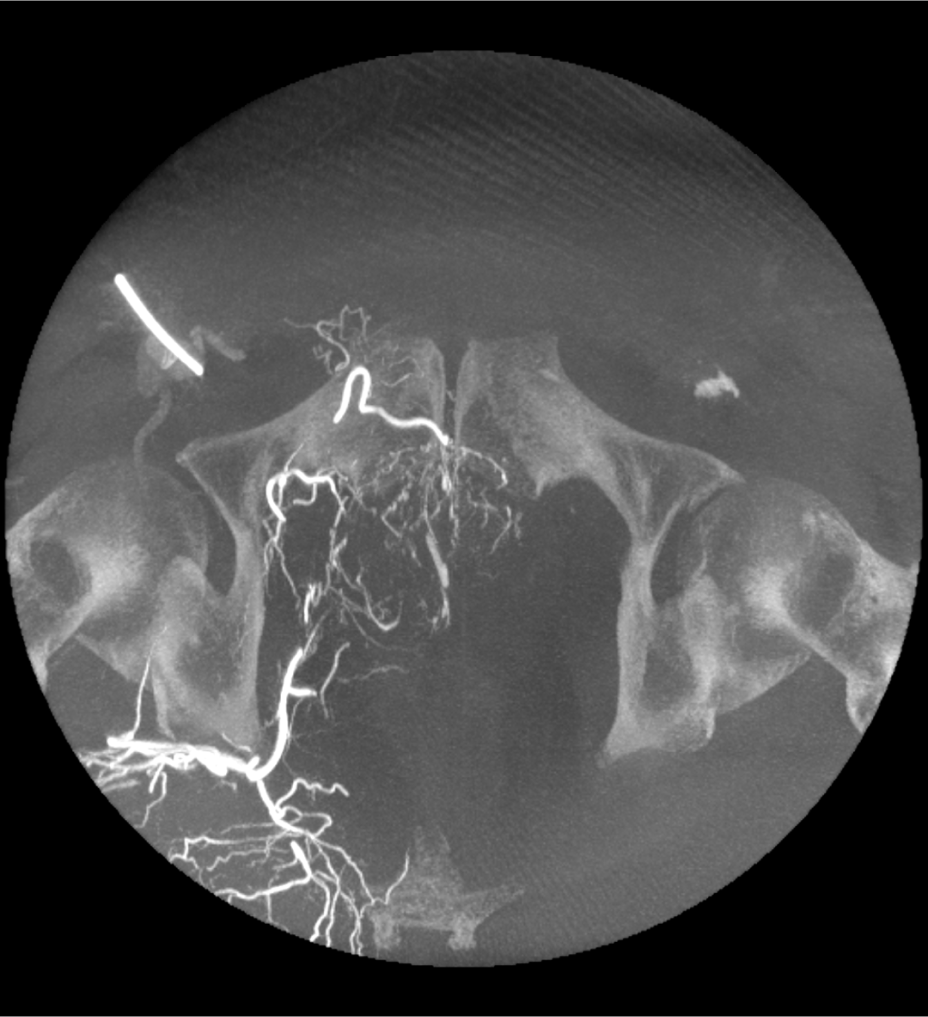

True Enhance DL

Designed to enhance what matters

True Enhance DL is a deep learning-based processing method intended for contrast enhancement of single energy images. True Enhance DL uses a dedicated Deep Neural Network (DNN) trained to estimate monochromatic, 50 keV GSI images from single-energy X-ray. This technology brings four deep learning models that the user can choose depending on different contrast enhancement phases by clinical tasks.

TrueFidelity DL

Deep learning for a deeper understanding

TrueFidelity™ DL is our state-of-the-art image reconstruction technology that uses a DNN to generate high-definition, low-noise CT images. It produces images with exceptional sharpness, low-contrast image quality performance and your preferred noise texture, at the same dose.¹